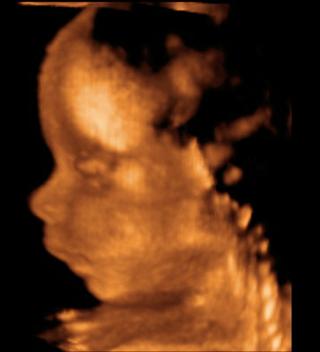

prave sme sa vratili z ultrazvuku, vsetko je v poriadku, sme zdravi a mala som dobreho tusaka ze budeme mat chlapceka 🙂 akurat som sa zabudla opytat kolko drobec vazi ☹

@vajanika27 nebud smutna,urcite je to valibuk 🙂 To si bola na 4D?

nie mame len fotky 🙂 ked nam prepol na 3D tak som ani nevedela rozoznat na co sa pozerame 😀